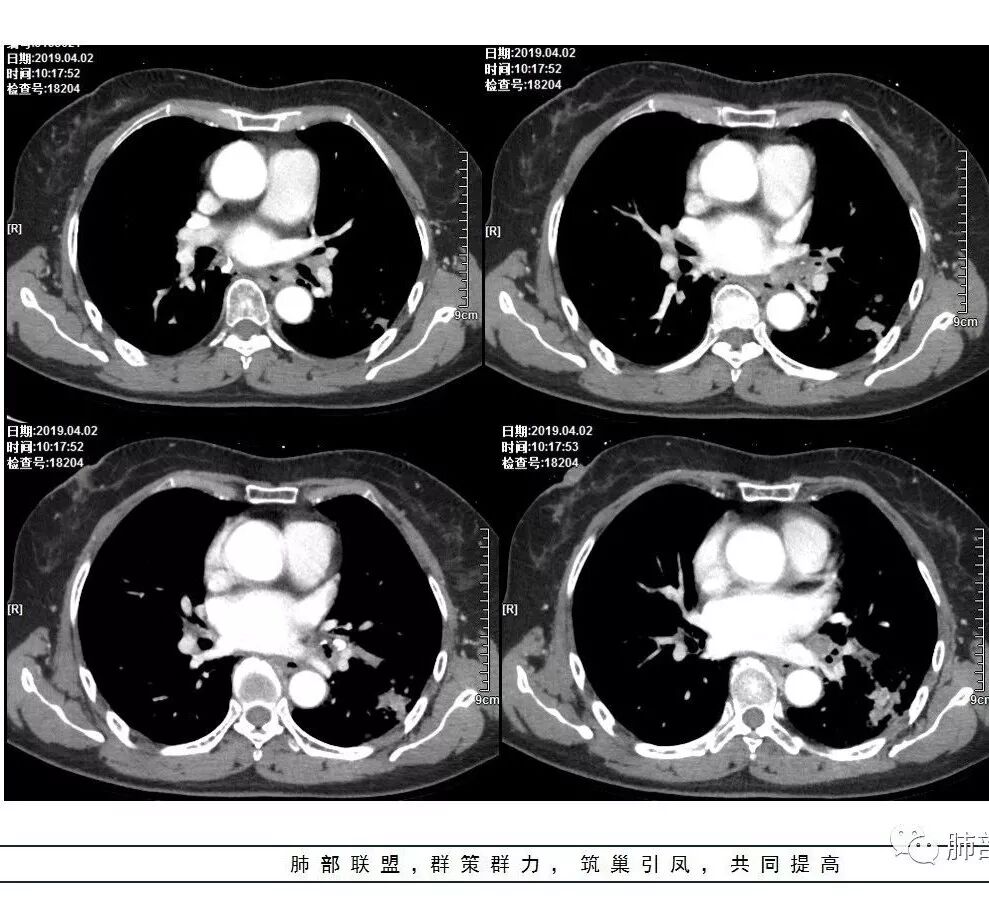

胸CT:左下叶实变影及磨玻璃影,小叶间隔增厚,内部支气管扩张、僵直。左肺门淋巴结肿大、钙化。考虑肺腺癌?合并感染

强化幅度太高了不是结核强化特点

左肺下叶多发结节影及磨玻璃影,抗感染病灶部分吸收,增强扫描速升速降,左肺门见环形强化淋巴结,病灶反反复复,考虑肺炎型肺癌。

胸CT:左下叶基底段支气管狭窄,沿支气管分布斑片实变影、网格影、磨玻璃影,支气管充气征,无重力效应,左肺门淋巴结肿大、钙化。

这是老问题:1、肺门区软组织密度影较弥漫;我们常规鉴别的就是结核?鳞癌?既往我们群里基本这两方向。2、弥漫的淋巴结钙化,加上马赛克灌注。马赛克灌注的原因是两个,一个是肺动脉的,一个就是小气道的问题。我们看增强的区域,没有看到栓塞,所以我倾向于小气道的问题,就是弥漫气道病变,慢性气道病变要考虑。我怀疑有没有淀粉样变性累及气道壁改变的可能。淀粉样变性是一个继发性病变,结核也可以,粉尘也可以。

这个病例支气管狭窄后扩张,肺门区有很多钙化的淋巴结,两肺弥漫的马赛克灌注,肺门淋巴结这么多,一个结核,一个尘肺,然后就是一个淀粉样变性,这几种最常见。鳞癌因为老年女性,除非吸烟,不太考虑,又不能绝对排除,所以就把鳞癌放到后。

实变部分强化很明显,怎么解释合理呢

结核强化可以这样吗?

肉芽肿期强化明显

肉芽肿是一个病理的概念,是炎症后期的修复,它的本质其实是迟发型过敏反应引起的炎症,在免疫应答中主要是一些巨噬细胞、上皮细胞来起作用,但是里面有非常丰富的毛细血管,所以这类病变强化很明显,影像上一般是结节状、团块状、大片状,整体有膨隆,边缘也有收缩,肉芽肿是一大类,影像有时很难区分,尘肺、结节病、淋巴瘤样肉芽肿都可以。常见的是炎性的,多见于结核,细菌性感染后期引起的类似op样,影像统称肉芽肿类病变,鉴别炎性还是恶性,要根据边缘、形态、周围结构及内部坏死情况。

今天这个病例有个明显的支气管狭窄,我倾向炎性,主要是和钙化淋巴结相关的,可能是继发的淀粉样变性。到底是什么感染,结核还是其他。我想看看复查后这个淋巴结,有没有突入到支气管腔内,如果有,他是继发于炎症的(比如中叶综合征,就是周围淋巴结压迫支气管,因为钙化淋巴结比较硬,支气管壁扛不住压力,突入支气管腔内,导致管腔狭窄,我们也称为结石征),如果没有,就和淋巴结关系不密切。之前有一例淀粉样变性的,淋巴结弥漫钙化,一种罕见的浆细胞型的CD。